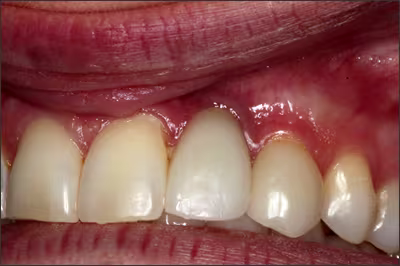

Leukoplakia

Leukoplakia occurs six times more frequently in smokers than non-smokers. It also has been shown that over 40% of smokeless tobacco users exhibit a lesion where the tobacco is held. Given the unpredictability of benign leukoplakia changing to a malignancy, these lesions must be carefully assessed.2,8